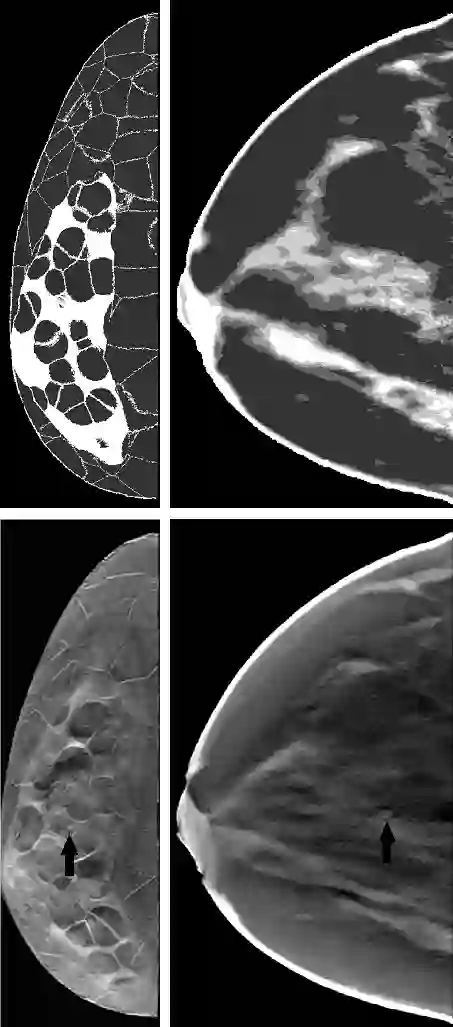

Purpose: Digital phantoms are one of the key components of virtual imaging trials (VITs) that aim to assess and optimize new medical imaging systems and algorithms. However, these phantoms vary in their voxel resolution, appearance, and structural details. This study aims to examine whether and how variations between digital phantoms influence system optimization with digital breast tomosynthesis (DBT) as a chosen modality. Methods: We selected widely used and open-access digital breast phantoms generated with different methods. For each phantom type, we created an ensemble of DBT images to test acquisition strategies. Human observer localization ROC (LROC) was used to assess observer performance studies for each case. Noise power spectrum (NPS) was estimated to compare the phantom structural components. Further, we computed several gaze metrics to quantify the gaze pattern when viewing images generated from different phantom types. Results: Our LROC results show that the arc samplings for peak performance were approximately 2.5 degrees and 6 degrees in Bakic and XCAT breast phantoms respectively for 3-mm lesion detection tasks and indicate that system optimization outcomes from VITs can vary with phantom types and structural frequency components. Additionally, a significant correlation (p= 0.01) between gaze metrics and diagnostic performance suggests that gaze analysis can be used to understand and evaluate task difficulty in VITs.